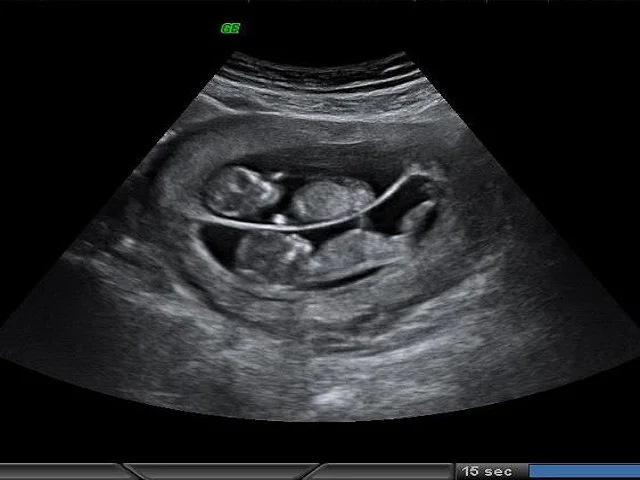

УЗИ

Монохориальную диамниотическую двойню можно определить с помощью ультразвукового исследования уже на 10-12-й неделе, так как это тот период, который позволяет визуализировать количество плацент. Саму многоплодную беременность устанавливают при УЗИ на 5-6-й неделе беременности.

С 14-16-й недели наиболее точно визуализируется, делят ли 2 плода 1 плаценту между собой. Узист может ошибиться, если 2 плаценты на картинке сливаются и кажутся одной.

На поздних сроках определяется половая принадлежность. Тогда же визуализируется, какая ожидается двойня: однояйцовая или разнояйцовая.

Монохориальной диамниотической двойне характерно образование анастомозов между сосудистыми системами каждого плода. Правильно выполненное УЗИ может стать ключевым видом диагностики.

На основании его результатов будет определена дальнейшая тактика ведения беременности, в том числе и при фето-фетальном трансфузионном синдроме, который требует своевременной терапии. При выявлении данной патологии исследование назначают значительно чаще с целью контроля вплоть до 28-й недели.